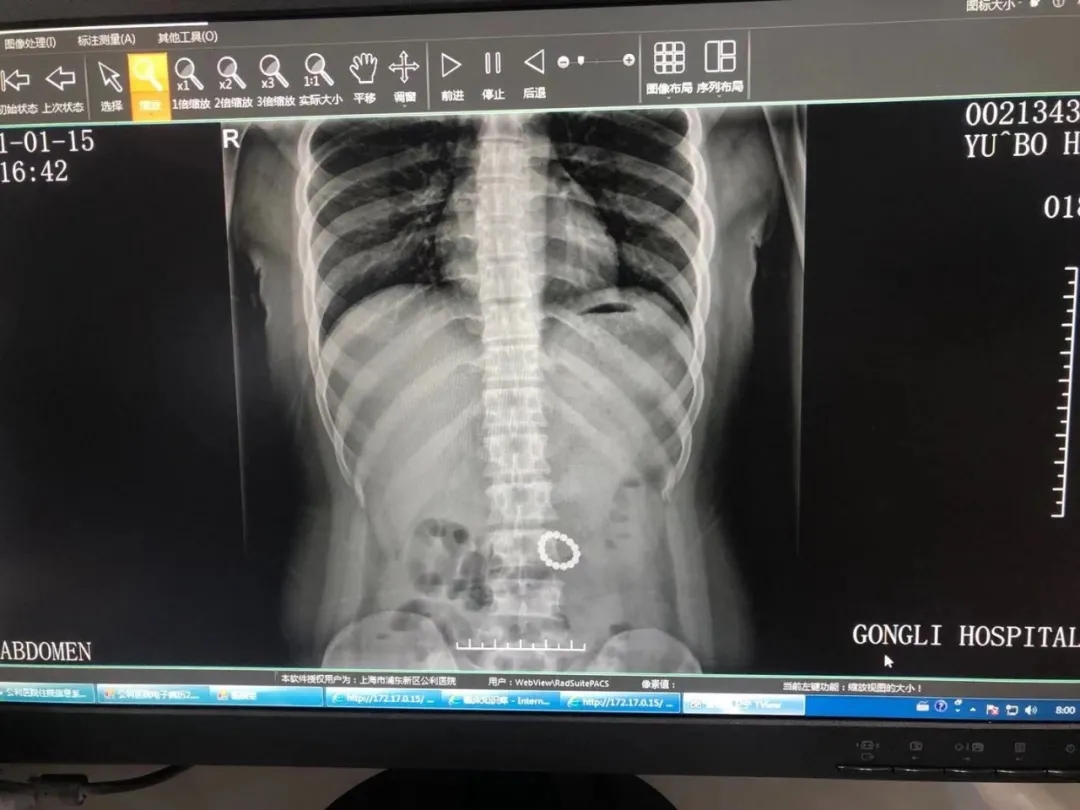

这天,公利医院普外科副主任医师陈志刚接诊了一位外地慕名而来的小患者。家长介绍,两天前,孩子不慎误吞了15颗小磁珠,当地医院曾尝试利用胃镜取出异物,但并未成功,心急如焚的家长赶紧带孩子来到上海就医。陈志刚发现孩子当时没有明显腹痛,当即为其复查了腹部平片和CT,并请影像科业务主任郑海宁一同读片。

郑海宁仔细读片后,发现异物已经进入孩子空肠上段。要知道,这一位置对于内镜来说难以企及,这可怎么办?是保守等待患者自行排出,还是立即手术?